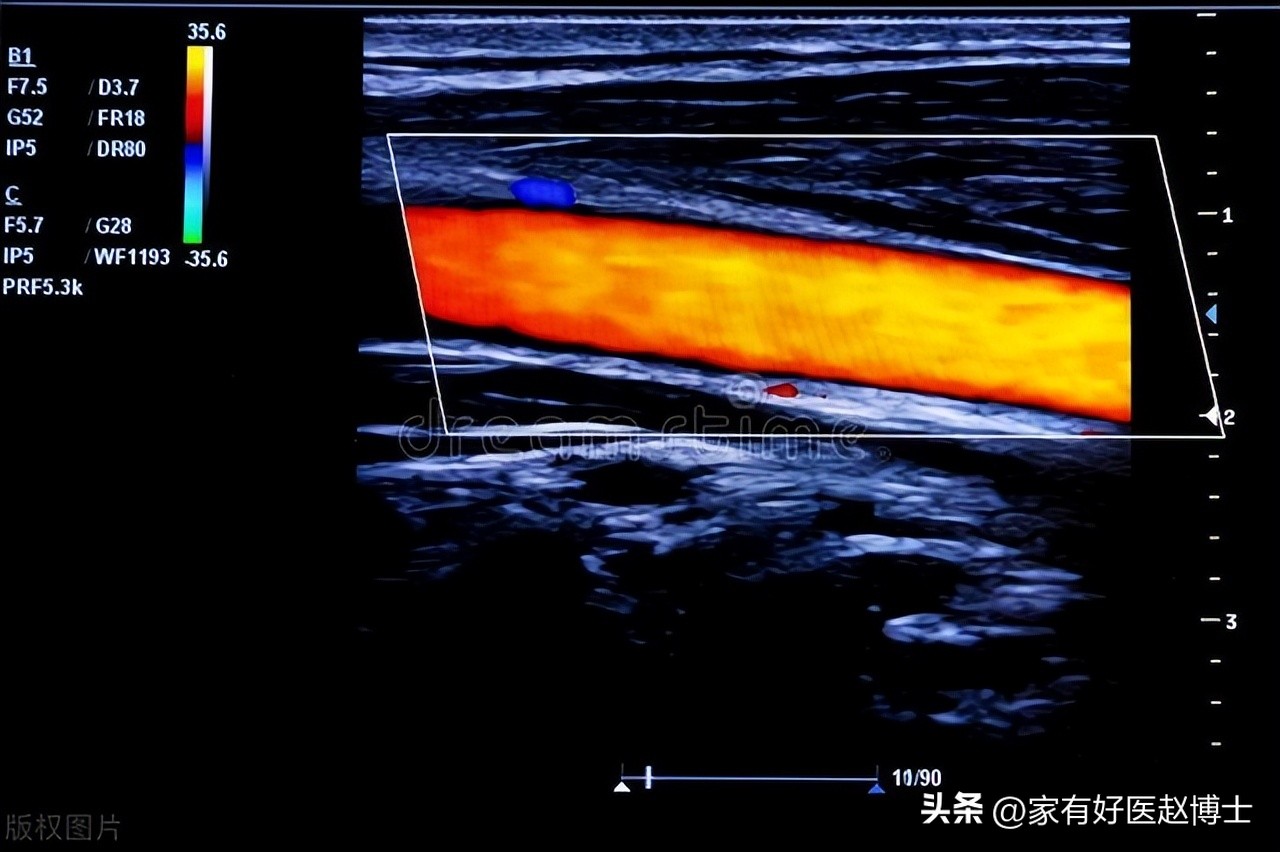

一 有没有引起“狭窄”?

2022版《动脉粥样硬化斑块的筛查与临床管理专家共识》明确指出:只要颈动脉斑块引起了颈动脉狭窄≥50%,那么,这种斑块就可以直接归类于“极高危”这个级别,属于危险程度最高的斑块。

原则上,这种对治疗决策有很大影响的情况,往往是超声报告里的“重中之重”。只要超声医生发现了斑块有引起血管狭窄的迹象,那么,就一定会在检查报告当中对此进行描述。

因此,假如您的超声报告里没有特别提到“斑块引起颈动脉狭窄”,那么,就往往意味着暂时还没有出现这种情况。